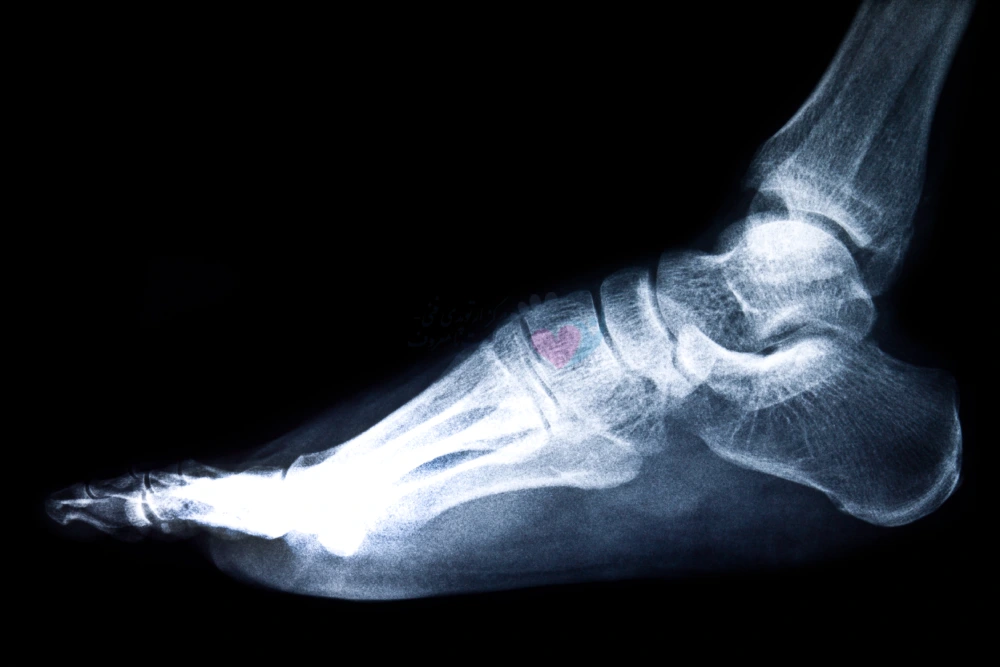

به طور کلی در استفاده از این اسکنرها، پاها در حین راه رفتن و ایستادن اسکن میشوند. جالب است که بدانید این اسکن در عرض چند ثانیه انجام شده و پس از آن تمام دادههای مربوط به کف پا و ساختار آن قابل بررسی هستند. در واقع میتوان گفت این نوع تجزیه و تحلیل پا، به پزشک ارتوپد کمک میکند تا اطلاعات فراوانی درباره ساختار استخوانی داخل پا، نقاط فشاری در زیر پا، نوع قوسهای پا و مشکلات و ناهنجاریهای حین راه رفتن درمورد بیمار، به دست بیاورد.